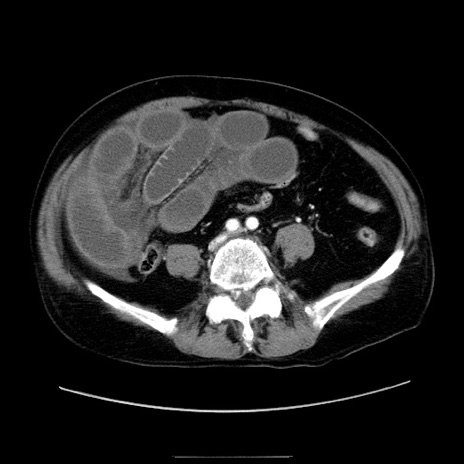

症例30(横断像)

【症例】80歳代男性

【主訴】臍周囲痛

【現病歴】約6時間前から臍下部痛が出現。次第に腹部膨隆・背部痛も生じてきたため来院。背部痛の場所は変化しない。

【身体所見】意識清明、BT 36.3℃、BP  131/87mmHg、P 87bpm、SpO2 100%(RA)、臍周囲自発痛・圧痛あり、反跳痛なし、自発痛部位に一致して板状硬あり、腹部膨隆、腸雑音減弱、CVA tenderness両側陰性。

【データ】WBC 19600、CRP 0.33